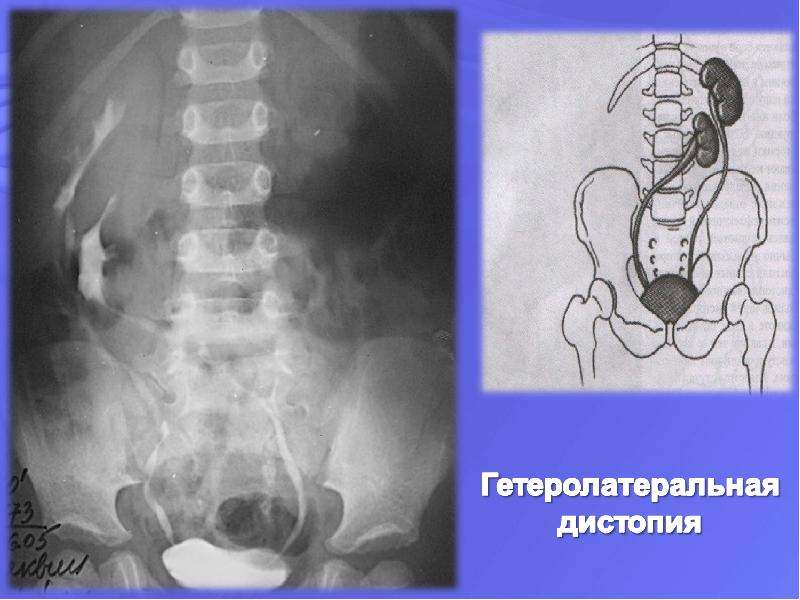

Экскреторная урография при нефроптозе: диагностические изображения